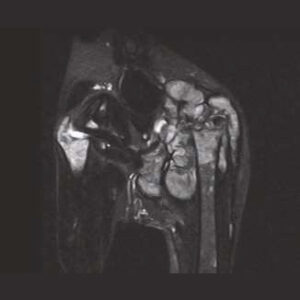

The PANION PRO comes with the double-pole open magnet design with a wide opening gap of 40 cm to accommodate large-sized animals on an efficient patient handling platform, the strongest gradient amplitude at 33mT/m and slew rate of 90 T/m/s, among all other open MRI systems, resulting in high spatial resolution of images in short scan time. The 6-direction patient table permits iso-centre imaging of all anatomical regions.

Clinical Images